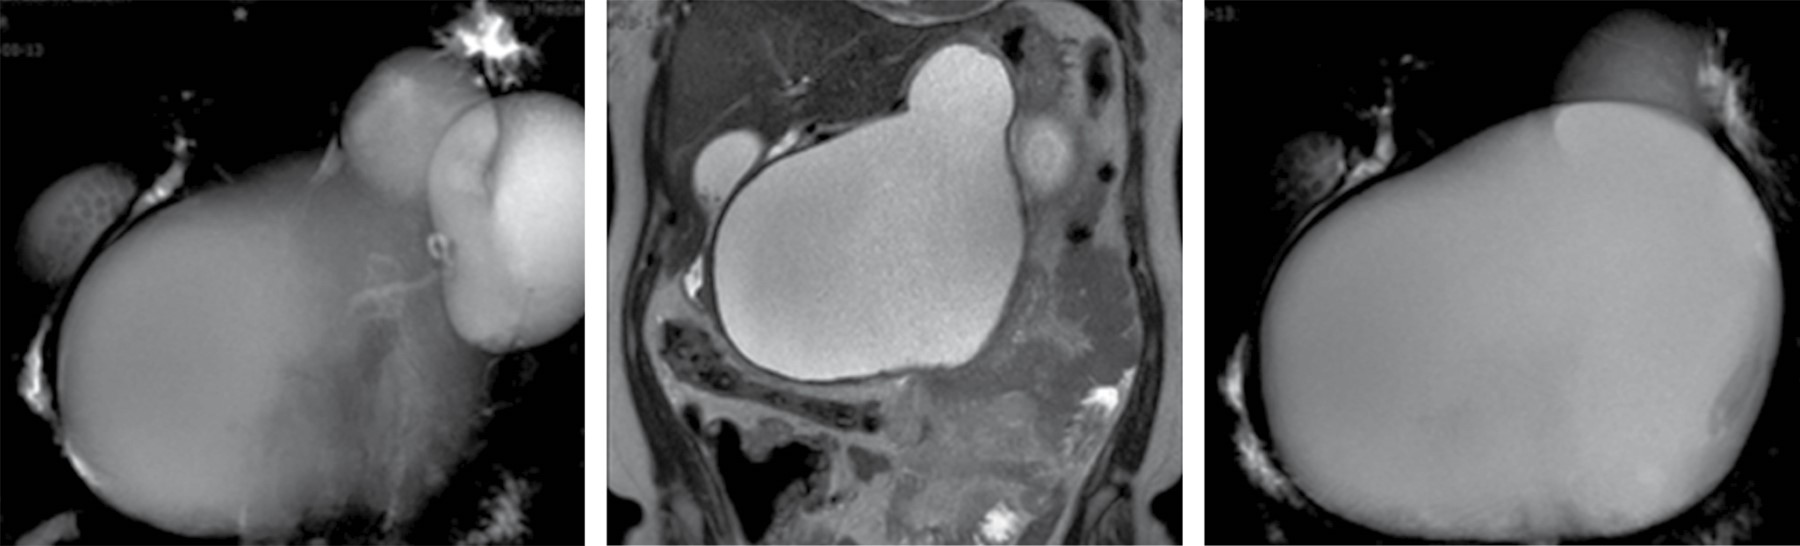

A magnetic resonance cholangiography was performed during her hospitalization. As a preoperative diagnostic approach, the following was found: a non-dilated intrahepatic biliary tract, a choledochal duct measuring 5.9 mm, a gallbladder of usual size with heterogeneous content due to the presence of multiple polyhedral images concerning biliary stones, and an extrahepatic tract displaced laterally by a lesion compatible with pancreatic pseudocysts. The pancreas had an altered morphology at the expense of two ovoid lesions, with well-defined lobulated borders, homogeneous hyperintense content in the T2 sequence, and a volume effect conditioning the opening of the duodenal arcade with lateral displacement of the stomach, limiting gastric distension. The largest lesion measured 178 × 179 × 155 mm with an approximate volume of 2,089 cm3, and the smallest lesion measured 56 × 76 × 95 mm in its principal axes with an approximate volume of 213 cm3. Before the surgical procedure, serum tumor markers showed an alpha-fetoprotein (AFP) 0.79 ng/mL, CEA 1.16 ng/mL, human chorionic gonadotropin (HCG) < 0.10 mIU/ml, CA-125 17.37 U/ml, CA15-3 16.2 U/ml and CA19-9 8.25 U/ml (Figure 3).

Figure 3